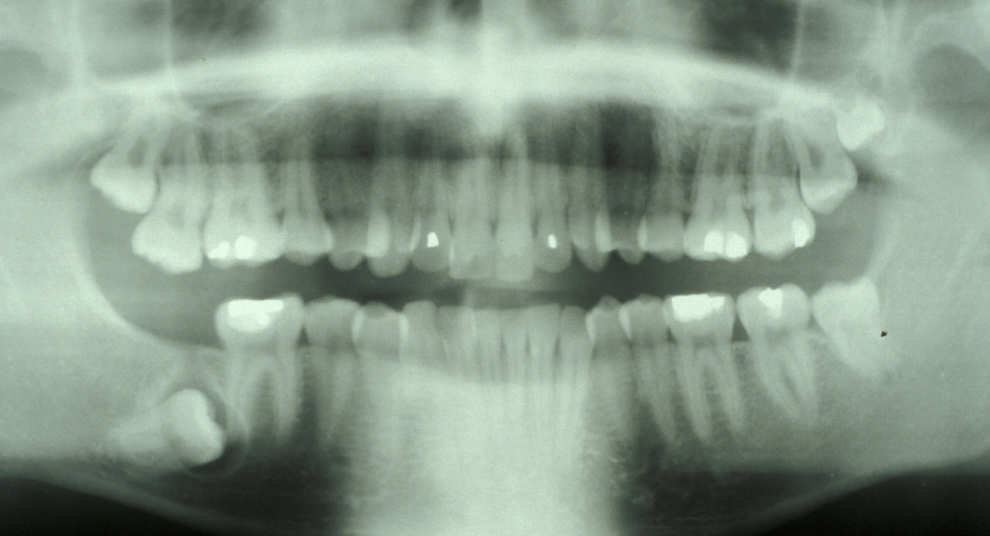

Assessment of the tooth is both clinical and radiographic. If somebody presents in pain, it is important to establish that this is coming from the third molar and not elsewhere. Pain is often vague, poorly localised and may be referred from another tooth, or as part of facial arthromyalgia (condition affecting the jaw joint). A dental panoramic radiograph is ideal as it helps to assess all the teeth at once. The health of the adjacent molars may influence the decision whether to remove the third molar or not. Large crowns or old restorations are all at risk of dislodgement during surgery. It is also worth considering whether alternative treatment options are available. For instance, pericoronitis due to an over-erupted upper third molar may be dealt with by extracting that tooth only, with or without operculectomy. In the presence of other teeth of poor prognosis, will it be better in the long term to save the third molar which may be used as a denture or bridge abutment in the future?

Having established that the wisdom tooth needs to be removed, other points in the assessment include:

- tooth position (vertical, mesioangular, distoangular, horizontal or across the arch).

- depth and degree of impaction;

- obstruction to eruption (what is the tooth impacted against?);

- root morphology (the curvature of the roots controls the path of withdrawal);

- relationship to the inferior dental nerve canal;

- associated pathology (for example, cysts);

- bone density;

- status of second molar tooth (in selected cases where this tooth has a poor prognosis it may be better to extract it and leave the third molar).

These points help to determine whether the tooth can be simply elevated or will need a surgical approach. A series of radiographs depicted in Figure 4 to Figure 8 illustrate these points further.